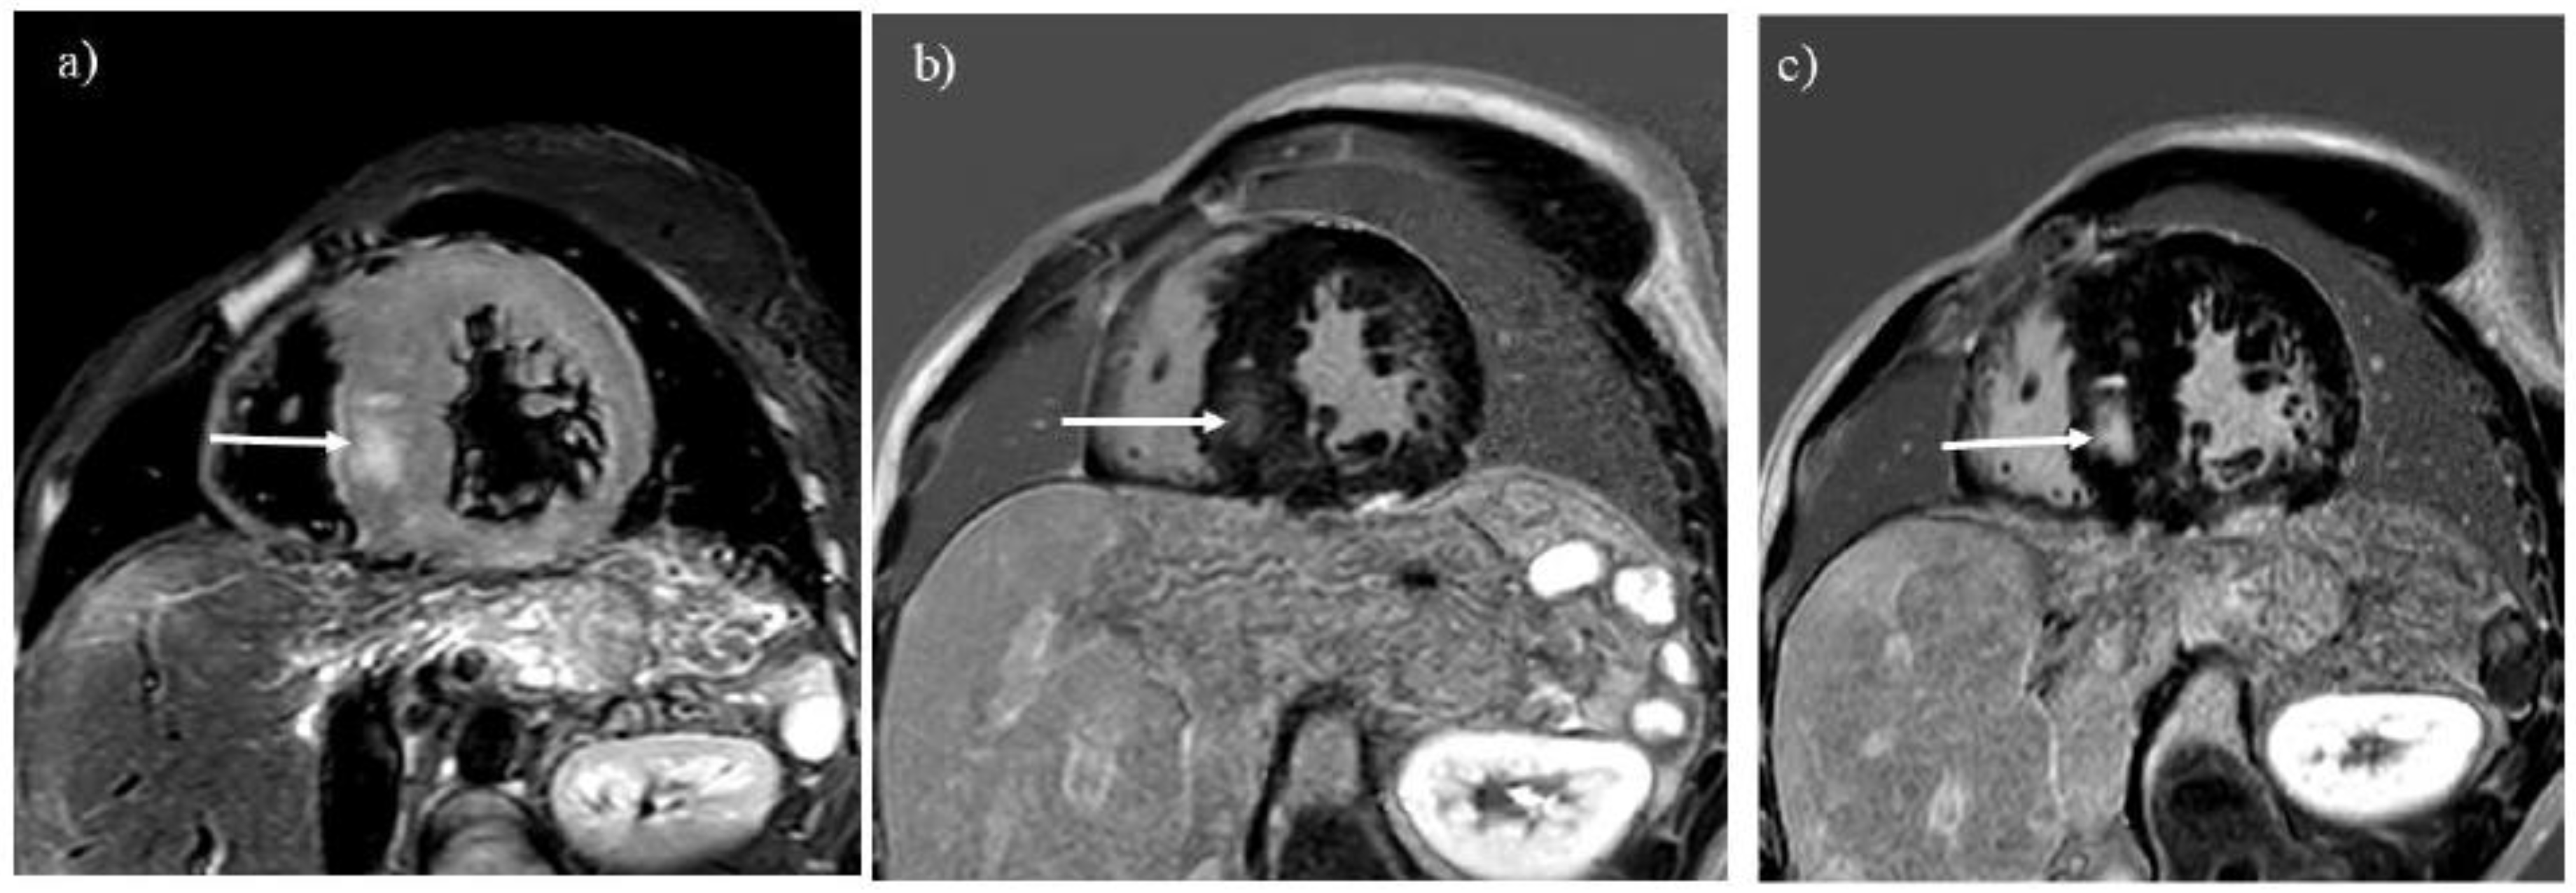

3.4. Myocardial Involvement

GSD type IIIa is known to involve the myocardium and can lead to sudden cardiac death because of severe myocardial hypertrophy or glycogen accumulation in the conduction system [1,2,4]. MRI is the best imaging tool for evaluating tissue characterization of the myocardium. Myocardial edema and scars associated with GSD type IIIa are visualized with T2-weighted and LGE imaging, respectively (Figure 4) [10,11,12,16]. LGE is useful for observing myocardial scars that can progress even after liver transplantation (Figures 4B and C). Differential diagnoses of myocardial involvement in GSD include hypertrophic cardiomyopathy, Anderson-Fabry disease, Noonan syndrome, and mitochondrial cardiomyopathies, which exhibit myocardial hypertrophy in children and young adults [11,20,21].

Figure 4. T2-weighted imaging (A) showed myocardial hypertrophy and edema in a 27-year-old man with glycogen storage disease type IIIa (arrow). He had undergone liver transplantation 8 years before. Late gadolinium enhancement (LGE) imaging (B) identifies a myocardial scar in the hypertrophied septum (arrow). The location of LGE is identical to that of myocardial edema (A, B; arrows). Progression of the myocardial scarring was observed at 30 years (C, arrow).